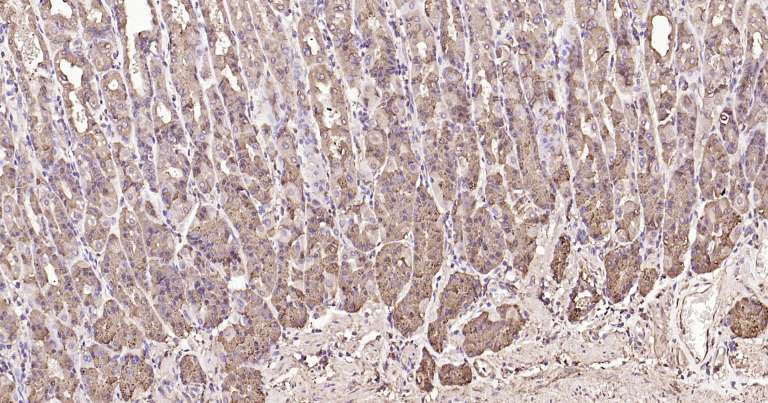

Immunohistochemical analysis of paraffin embedded human stomach tissue slide using IHC0272H (Human Calreticulin IHC Kit).